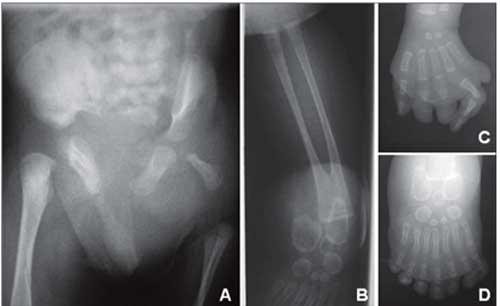

L’artrite reumatoide è una malattia infiammatoria cronica che colpisce in particolare le articolazioni, ma spesso coinvolge cute, occhi, polmoni, cuore e reni e peggiora progressivamente se non si interviene subito. Provoca dolore e gonfiore a mani, piedi, dita, ginocchia, gomiti e collo. Il processo infiammatorio causa l’erosione e la graduale distruzione della cartilagine e può arrivare fino all’osso. La malattia è causata da una risposta immunitaria anomala dell’organismo, che innesca un meccanismo di auto-distruzione dei tessuti articolari.